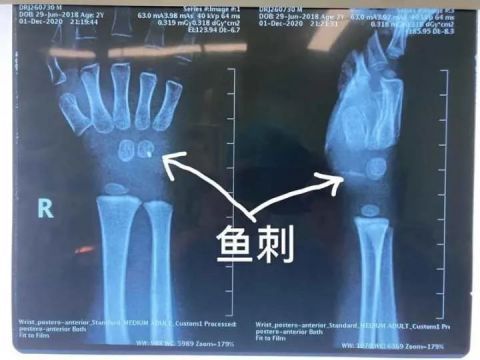

儿童活泼好动,喜欢探索新鲜事物,但自我保护意识差,有时家中不注意的物品会一不小心给孩子带来伤害。近日,骨科就接诊了一位被鱼刺扎伤手腕的小患者。原来,调皮的元元(化名)在家拿着鱼玩耍,结果不小心忽然摔倒,鱼刺深深地扎进了他的手腕。由于伤口情况复杂,辗转多家医院均无法手术,最后来到了杭州市儿童医院骨科。拍片检查后发现,鱼刺已经深及元元的手腕内部约一厘米左右的位置。虽然体表伤口细小,但是内部伤口附近神经、血管交织错杂,如不及时取出鱼刺,会严重影响孩子的手腕功能。

手术室里,骨科医生采用C臂机仔细定位后探查鱼刺,发现鱼刺像一把锋利的小匕首,切断了肌肉和腕横韧带,刺入到腕管内,毗邻正中神经和肌腱,并且鱼刺已断成两截,这无疑大大增加了取出的难度。在小心翼翼地取出鱼刺后,医生再次探查周围神经、血管、肌腱,确定没有残留及其他损伤后,缝合伤口。经过两个多小时,终于为孩子解决这恼人的“不速之客”。